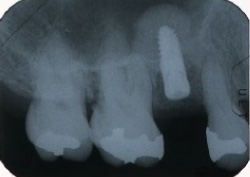

●エムドゲイン塗布後、徐々に影が、うすくなってきています。

●影が無くなり、骨ができています。